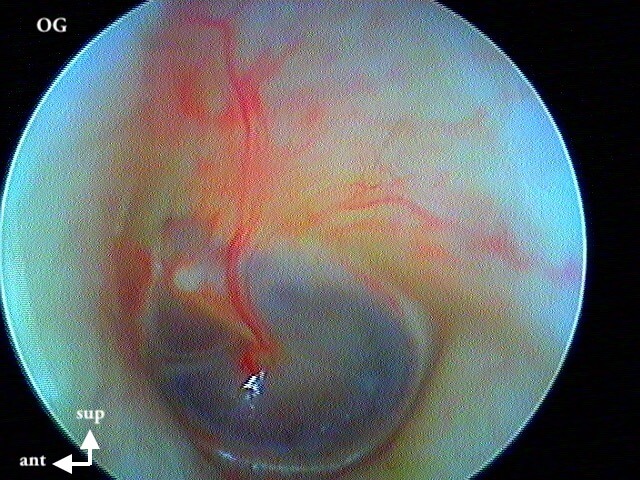

Tumeur rouge battante derrière un tympan normal, à ne pas confondre avec une otite séromuqueuse dont le liquide "bat" avec les battements des vaisseaux intratympaniques.

{youtube}qxcrkzyBCXg{/youtube}

Ici une oreille droite, ce n'est pas une sténose de la paroi postérieure du CAE de l'oreille droite car elle "battait", j'ai suspecté une déhiscence méningée...